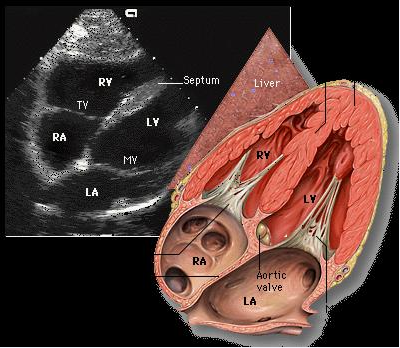

(图) 心底短轴切面 (二维超声心动图)

图片尺寸944x727

经典心脏超声切面图及解剖解释

图片尺寸893x584